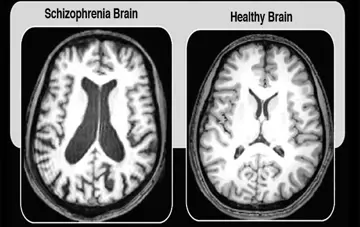

تفاوت در مغز بیماران دچار اسکیزوفرنی